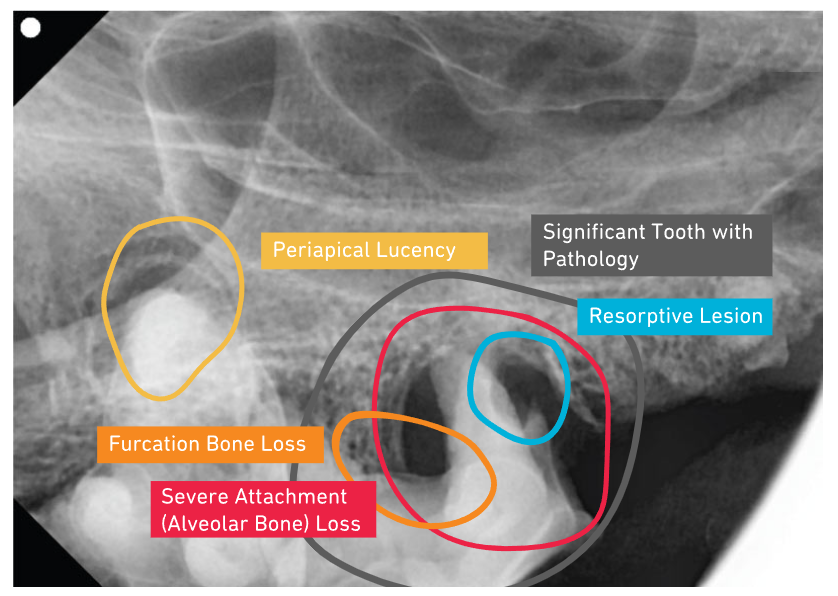

SignalSMILE's patenterade AI-teknologi för veterinärer använder maskininlärning för att i realtid bedöma röntgenbilder av sällskapsdjurs tänder för normalt och onormalt, för att hjälpa praktiker i diagnosprocessen.

Vår patenterade AI upptäcker det normala och onormala för de 7 vanligaste tandpatologierna och underlättar beslutsfattande vid vårdpunkt.

Medan du utför en grundlig rengöring arbetar SignalSMILE'S AI aktivt i bakgrunden för att ge resultat av de 7 vanligaste tandpatologierna.

Fatta informerade beslut

Att fatta beslut kring utdragningar bör inte tas lättvindigt. Med SignalSMILEs stöd kan du vara trygg i ditt beslutsfattande kring kirurgiska ingrepp för tänder med patologi.